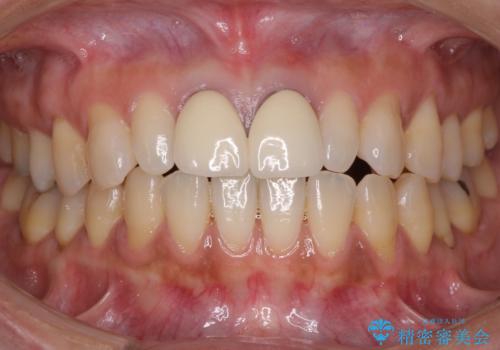

前歯をメタルフリーに 根管治療で不安を取り除いてから

セラミック治療と根管治療を行いました。

患者様は、もともと奥歯の虫歯を心配してご来院されましたが、前歯に問題が見つかりました。

金属を使用したメタルボンドクラウンが入っていたため、いつかオールセラミックにしたいときに根管治療も行ったほうが良いとご提案し、今回行いました。